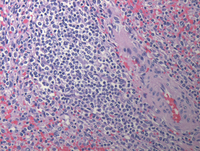

HE images of splenectomy

At low power, multiple discrete white pulp nodules are noted. On higher power these nodules are monotonous with replacement of the white pulp by small to medium sized lymphoid cells with occasional plasmacytoid cells.